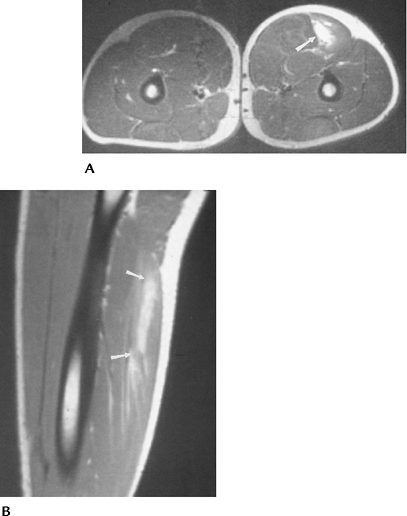

![]() |

FIGURE 4-22 Axial (A) and sagittal (B) T2-weighted images of a Grade 1–2 strain of the hamstring muscles (arrows).

|

FIGURE 4-23 Coronal (A) and axial (B) T2-weighted images of an adductor muscle tear (arrows) with a central hematoma.